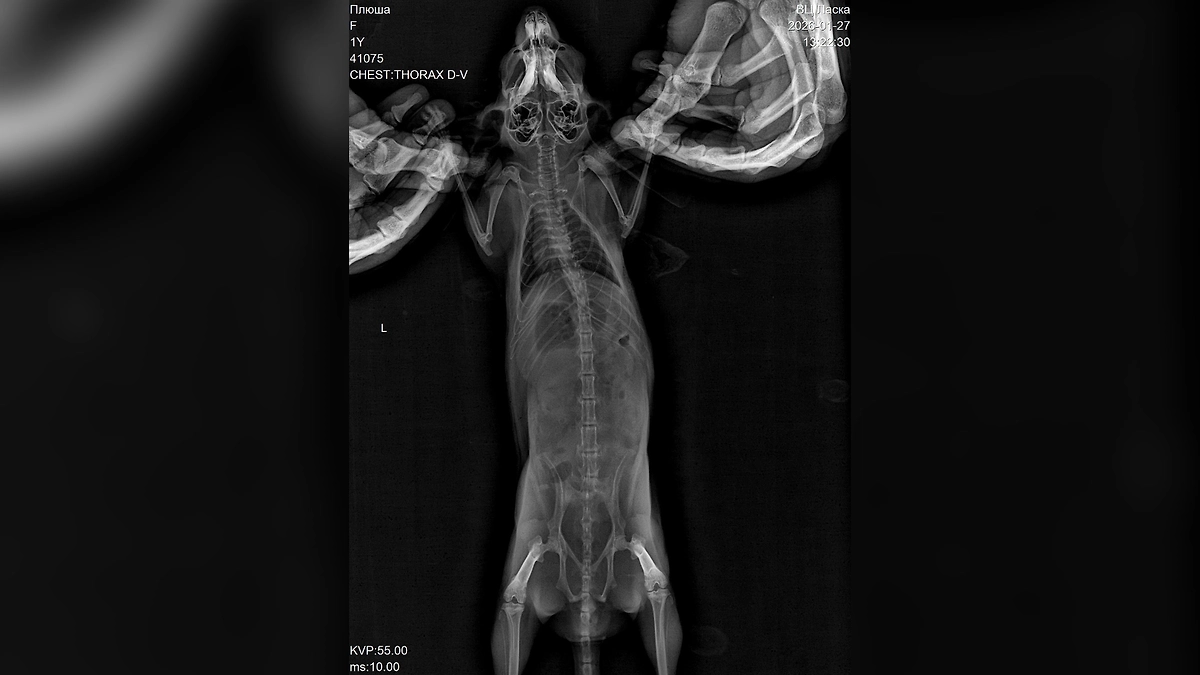

«За неё боролись около четырёх часов, но к сожалению, травмы оказались несовместимыми с жизнью. Диагноз — черепно-мозговая травма и отёк головного мозга», — написал он.

По словам Билана, он сначала предположил, что шиншилла могла получить травмы из-за кота Шахтёр, поскольку он хищник. Однако, по всей видимости, Плюша самостоятельно выбралась из клетки и с разбега врезалась в панорамное окно, что принесло тяжёлые травмы. Артист обратил внимание на то, как важно заранее понимать, с какими трудностями можно столкнуться, когда заводишь подобное животное.